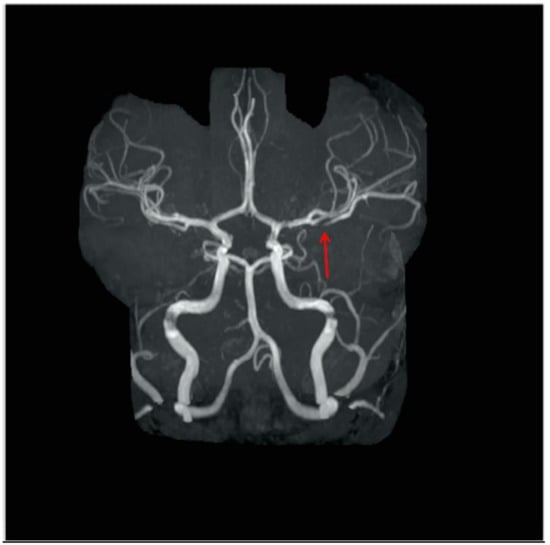

2. Patient Description

| Baumgartle * | 2016 | M/12 years old | Headache, facial drooping, slurred speech and right sided weakness | Left MCA infarction |